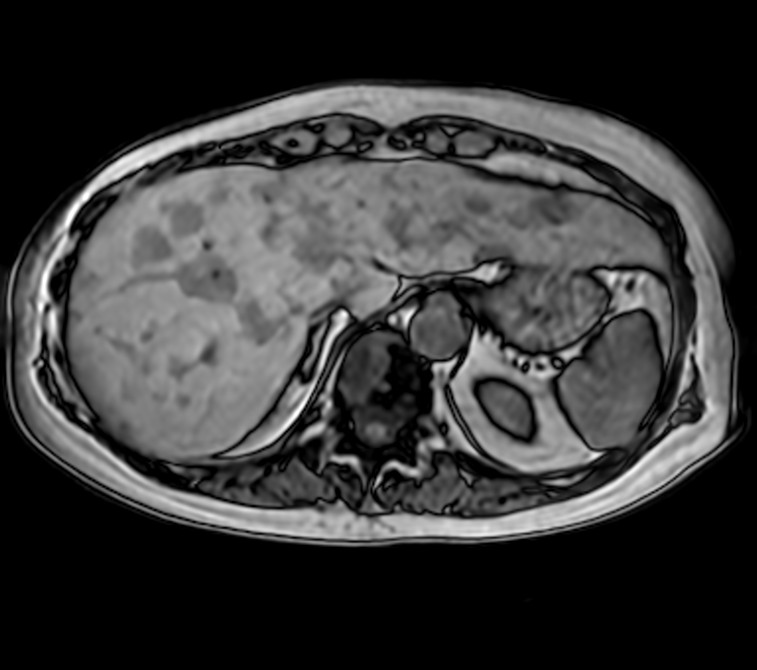

mDIXON Quant